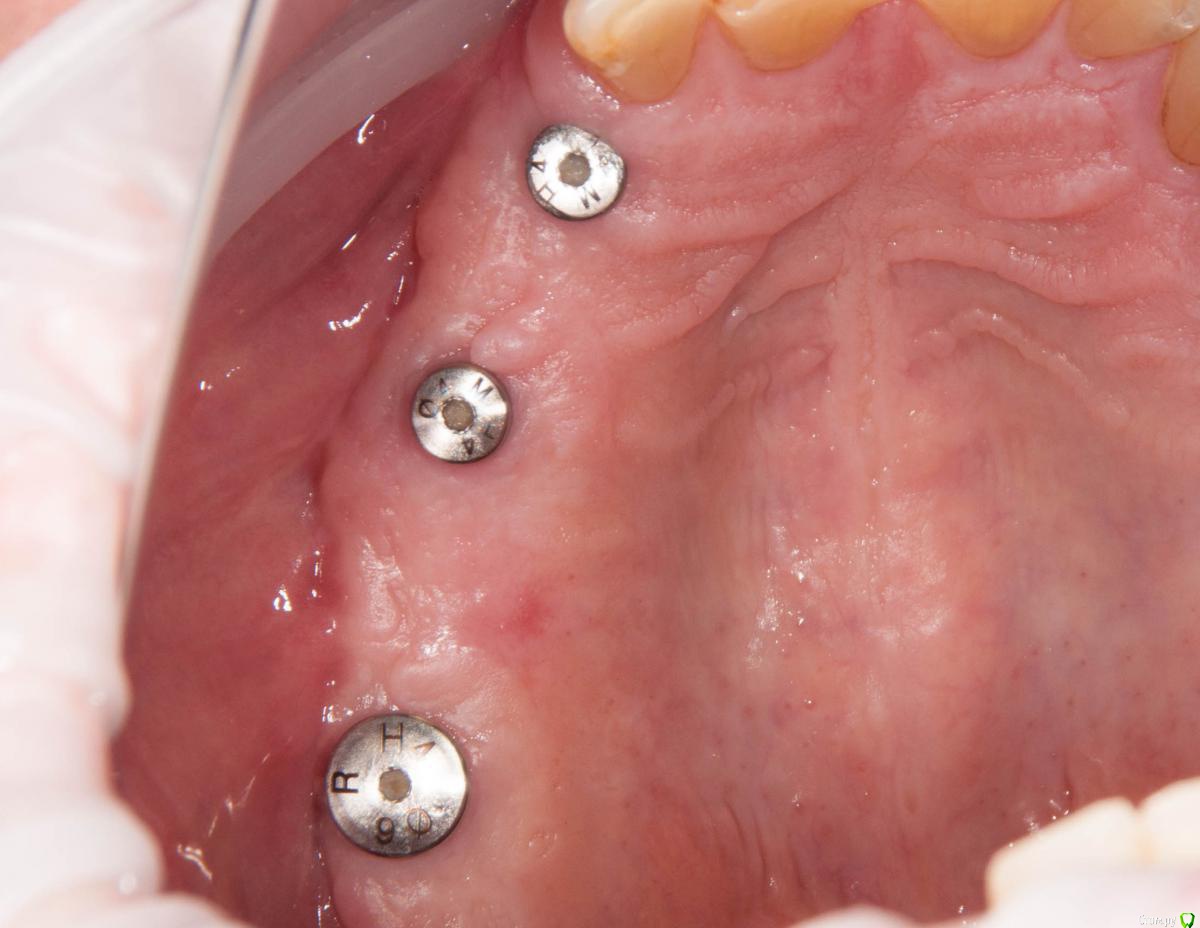

kamranchick Опубликовано 4 мая, 2018 Поделиться Опубликовано 4 мая, 2018 Обратился пациент после очередной халтуры которыми радуют меня коллеги из соседних клиник)фотопротокол ни как у Сашки Гудкова но более-менее понятно))Обратился пациент, в соседней клинике удаляли зуб, корень протолкнули в пазуху, далее пациент попал в ЧЛХ, там сделали радикальную гайморотомию, все достали, и вот попал пациент ко мне, так как в другой клинике сказали что у вас тут залу*а, а не кость, ну и погнали.1. пытался остро отслоиться, перфа на перфе, закрывал prf, мембранами, губками, стики бон + синус имплантация. ожидание 9 месяцев2. Пластика мягких тканей ожидание 2 месяца. 13 Ссылка на комментарий

Irouil Опубликовано 5 мая, 2018 Поделиться Опубликовано 5 мая, 2018 Гребень, конечно, был ужасный. Симпатично. Почему Паллачи? Ссылка на комментарий

kamranchick Опубликовано 5 мая, 2018 Автор Поделиться Опубликовано 5 мая, 2018 Гребень, конечно, был ужасный. Симпатично. Почему Паллачи?Я бы не сказал что это прям Палаччи)бугра нету так такого... плюс тут апикально надо было смещать, было 2 вариант, стрип, либо сдт около формиков, решил остановиться на таком варианте. Ссылка на комментарий